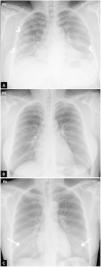

Figura 2.Hallazgos típicos de la neumonía COVID-19. A) Mujer de 47 años con sospecha clínica de enfermedad COVID-19. Radiografía de tórax posteroanterior (PA). Patrón intersticial-reticular de predominio periférico (flechas). B) Misma paciente que en imagen A. Radiografía de tórax PA realizada 3 días después. PCR positiva para SARS-CoV-2. Aunque la radiografía está menos inspirada, se objetiva la aparición de tenues opacidades alveolares (flechas punteadas) redondeadas bilaterales y periféricas. C) Varón de 57 años con disnea y PCR positiva para SARS-CoV-2. Opacidades periféricas bilaterales en campos superiores, medios e inferiores (puntas de flecha). D) Varón de 45 años con disnea y COVID-19 confirmada con PCR. Radiografía de tórax anteroposterior con múltiples áreas de consolidación confluentes difusas bilaterales que afectan extensamente a ambos pulmones. Nótese la presencia de dos vías venosas centrales, una yugular izquierda y otra subclavia derecha (flechas blancas) y de sonda digestiva (flecha negra).

Hallazgos típicos o aquellos que se han asociado comúnmente en la literatura científica a COVID-19 (fig. 2). Incluyen el patrón reticular, las opacidades en vidrio deslustrado y las consolidaciones, con morfología redondeada y una distribución multifocal parcheada o confluente. La distribución suele ser bilateral y periférica y predominantemente en los campos inferiores23 (fig. 2). El diagnóstico diferencial incluye la neumonía organizada, la toxicidad farmacológica y otras causas de daño pulmonar agudo. Entre la primera y la tercera semana desde el inicio de los síntomas, los hallazgos radiológicos típicos pueden evolucionar hacia una enfermedad difusa. Esto se relaciona con una situación clínica grave de hipoxemia y el principal diagnóstico diferencial es el síndrome de distrés respiratorio agudo (SDRA).

Hallazgos indeterminados o aquellos que pudiendo presentarse en casos de neumonía COVID-19 pueden tener otras causas. Incluyen las consolidaciones o las opacidades en vidrio deslustrado con distribución unilateral, central o en los lóbulos superiores (fig. 3A). El diagnóstico diferencial incluye otras infecciones y el edema alveolar.

Figura 3.Hallazgos atípicos de neumonía COVID-19. A) Neumonía lobar. Varón de 28 años con clínica compatible con enfermedad COVID-19 y PCR positiva para SARS-CoV-2. Radiografía de tórax en proyección posteroanterior (PA). Afectación del lóbulo superior derecho (flecha). B y C) Afectación bilateral y derrame pleural. Varón de 17 años con fiebre y PCR positiva para SARS-CoV-2. Radiografía de tórax PA (B) y lateral (C). Tenues infiltrados bilaterales en campos inferiores (flechas) con mínimo derrame pleural en el seno costodiafragmático posterior izquierdo (punta de flecha).

Hallazgos atípicos o aquellos poco frecuentes o no descritos en neumonía COVID-19. Incluyen la consolidación lobar, el nódulo o la masa pulmonar, el patrón miliar, la cavitación y el derrame pleural, descrito solo en el 3% de los pacientes23 y más típico de la enfermedad avanzada (fig. 3B y C).